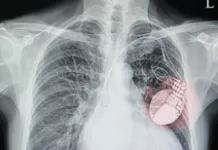

Cholesterol-lowering statins are powerful agents for preventing heart attack in men and women with heart disease. Statins also have unrelated benefits, such as lowering the risk for Alzheimers disease and age-related decline in lung function. But they can have adverse effects, too. A meta-analysis of five major trials (Archives of Internal Medicine, January 9, 2012) found that statins increased the risk of diabetes in postmenopausal women. The effect was consistent with all statins. So should you stop taking your statin if you are at high risk for heart disease, or have been already been diagnosed? Cleveland Clinic cardiologists say no.